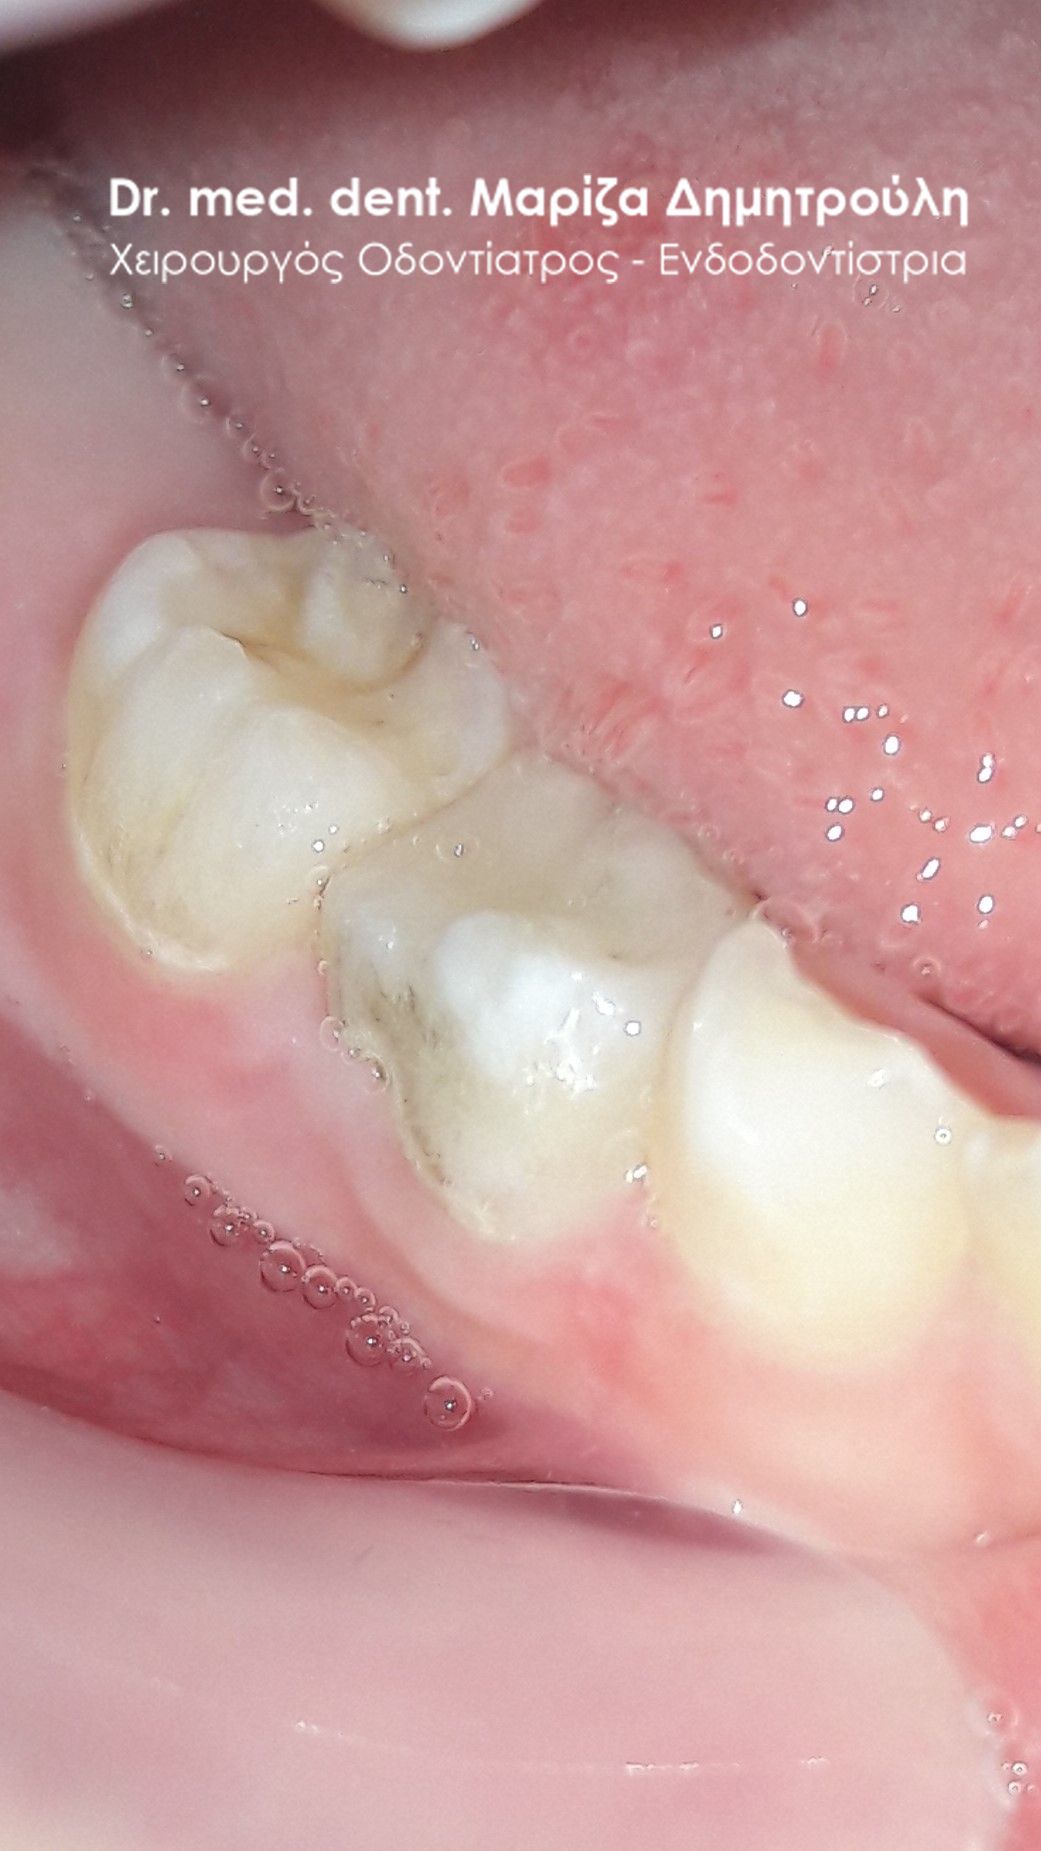

Περιστατικό – Ολική αποκατάσταση παιδικού στόματος

Η μικρή ασθενής προσήλθε στο ιατρείο παρουσιάζοντας εκτεταμένες τερηδονικές βλάβες σε όλα τα πίσω δόντια. Η μητέρα επιθυμούσε τη διατήρηση των παιδικών δοντιών στο στόμα του κοριτσιού και ήθελε να αποφύγουμε την εξαγωγή τους. Ξεκίνησε η θεραπεία των δοντιών ανά τεταρτημόριο. Σε κάποια δόντια λόγω της βαθιάς και εκτεταμένης τερηδόνας (που έφτανε στο ύψος του πολφού) πραγματοποιήθηκε πολφοτομή. Όλα τα δόντια αποκταταστάθηκαν με λευκά σφραγίσματα σύνθετης ρητίνης.

ΠΡΙΝ

ΜΕΤΑ